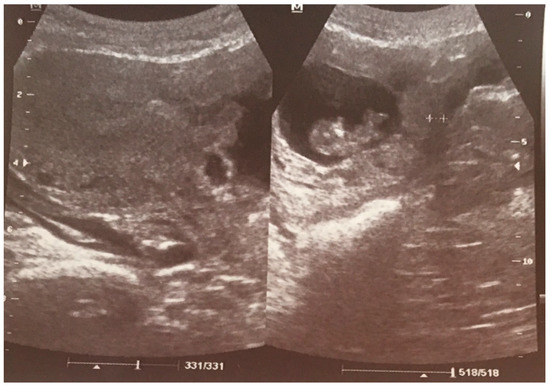

- 1

- an empty uterine cavity with clear endometrium and empty endocervical canal,

- 2

- the detection of a gestational sac within the anterior lower segment of the uterus embedded in the cesarean scar,

- 3

- an absent or thin (<5 mm) myometrium layer between the gestational sac and the bladder,

- 4

- 5

- the pathologies of the adnexa should be excluded, and there should be no detection of fluid in the Douglas pouch unless in the case of a massive hemorrhage or rupture of the uterus [5].